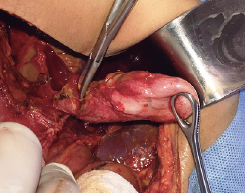

Imágenes y Cirugía

|

Natalia González Alcolea, María Dolores Chaparro Cabezas, Félix Martínez Arrieta, Victor Sánchez Turrión